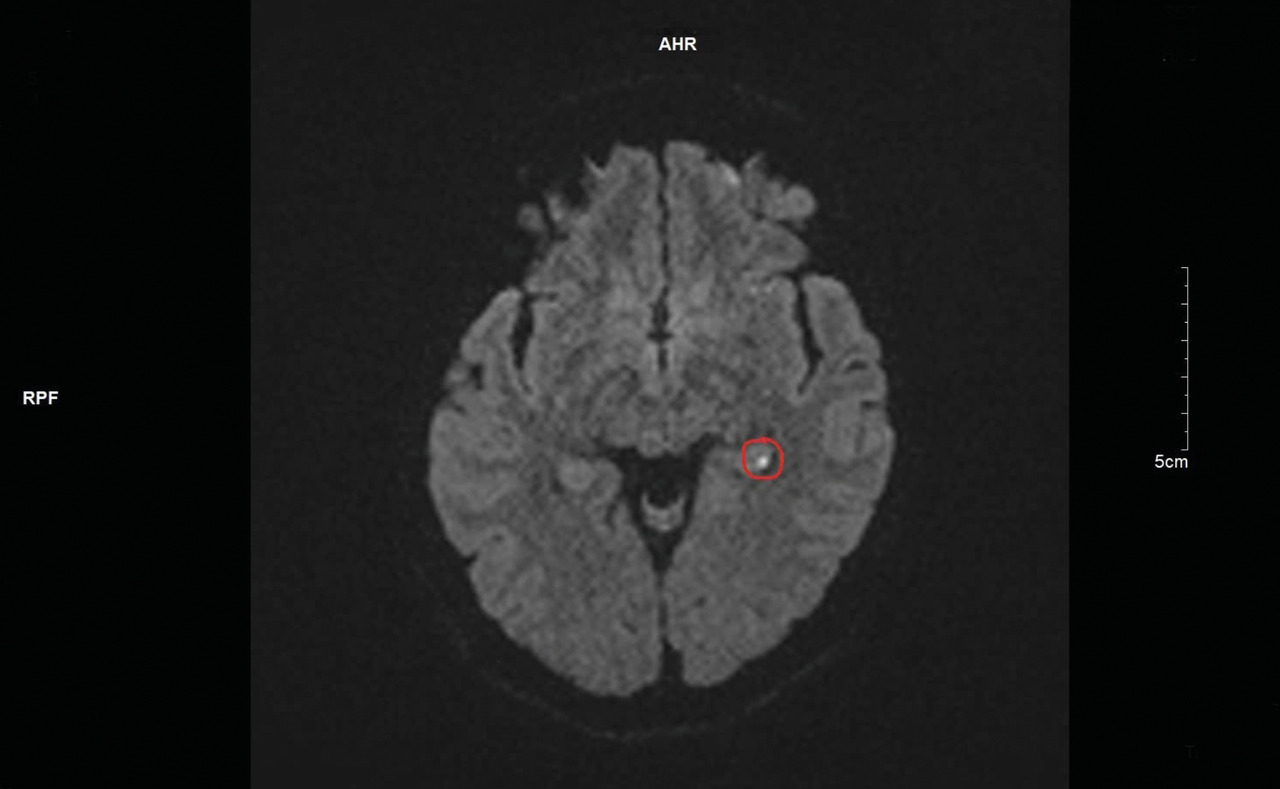

Une imagerie par résonance magnétique (IRM) cérébrale est réalisée quarante-huit heures après l’épisode, mettant en évidence un hypersignal punctiforme en séquence diffusion (fig. 1) et en hyposignal ADC (apparent coefficient diffusion) [fig. 2] localisé à la partie interne du lobe temporal gauche.

L’IRM permet de mettre en évidence les signes caractéristiques à la partie interne du lobe tempo­ral (hypersignal diffusion et hy­posignal ADC), avec une détection optimale deux et trois jours après l’épisode. Il est important de préciser au radiologue la nécessité de réaliser des coupes fines de la région.